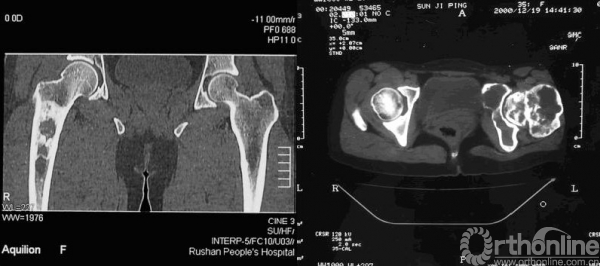

CT检查

CT检查和X线相似,主要是磨砂玻璃状、囊性变和膨胀性改变,但影像更直观,特别是对骨皮质的破坏显示的更清楚(图7),为手术入路提供了一定的信息。

图7 CT示高、低密度混杂,有囊性变和硬化边缘

MRI检查

MRI表现比较复杂,根据病灶内所含组织的比例不同,表现也不同,多数表现为T1WI和T2WI呈不均匀的低信号,T2WI压脂像上呈中等信号(图8),病灶内有出血或积液时信号明显增高,MRI非常敏感,可早期诊断,并能清楚的确定肿瘤的范围,但对骨皮质的显示不清楚(图9)。